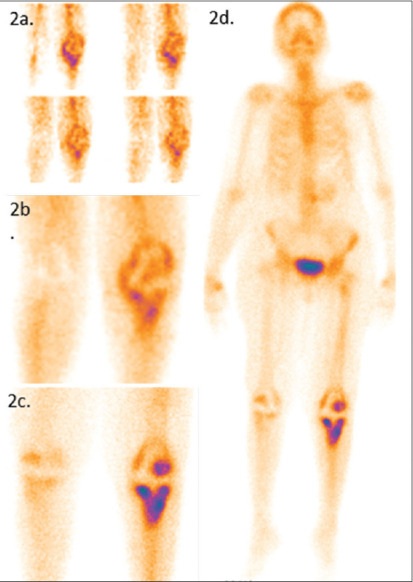

Donna di 58 anni, sottoposta a sostituzione totale del ginocchio sinistro, si è presentata con dolore in sede chirurgica.

La radiografia del ginocchio è risultata nella norma e la VES era lievemente elevata. La paziente è stata sottoposta a scintigrafia ossea trifasica con 99mTc-MDP.Le immagini di flusso (2a) hanno mostrato un’aumentata vascolarizzazione nel ginocchio sinistro e l’immagine di blood-pool (2b) ha evidenziato un aumentato accumulo del tracciante nella stessa sede. L’immagine statica tardiva dell’articolazione del ginocchio (2c) e l’immagine whole-body (2d) hanno mostrato un diffuso aumento della captazione all’interfaccia osso-protesi nella componente tibiale della protesi. Diagnosi: infezione protesica.